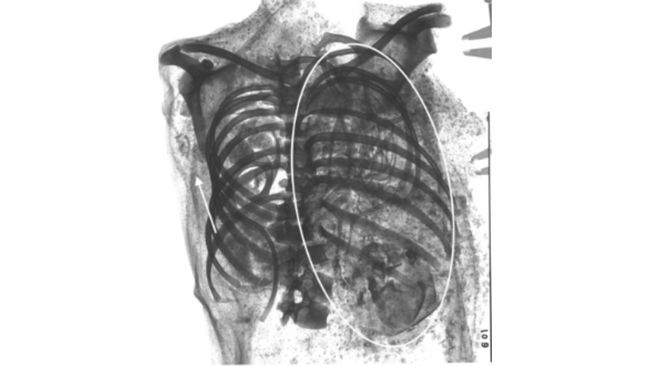

Temuan mumi mesir yang meninggal saat melahirkan. Foto: Margolis and Hunt, 2023 via Live Science

Gambar 3D menunjukkan sisa-sisa janin yang tidak disebutkan dalam catatan sebelumnya, telah bersarang di dada gadis itu. Margolis dan David Hunt, salah satu penulis studi dan antropolog di GWU, melakukan rontgen pada mumi tersebut untuk mendapatkan gambaran yang lebih jelas tentang sisa-sisa janin.

Margolis dan Hunt menemukan bahwa gadis tersebut meninggal saat melahirkan setelah kepala janin pertama terperangkap di jalan lahir. Kepala janin yang keluar dari rahim saat melahirkan biasanya diselipkan ke dadanya untuk memungkinkan jalan melalui panggul, menurut penelitian tersebut. Para peneliti berpendapat bahwa dalam kasus ini, kepala janin tidak terselip dalam posisi yang terlalu lebar untuk dilewati dan menjadi tersangkut.